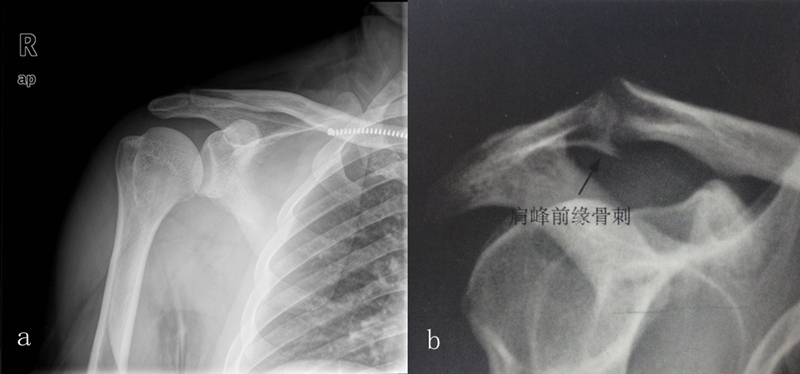

1、X线检查

X线检查用来评估肩峰形态,肱骨头和肩盂的关系,以及除外其他疾病。

图15 a.正常肩关节 b.肩峰撞击

图16 巨大肩袖损伤,肩峰下间隙<9mm